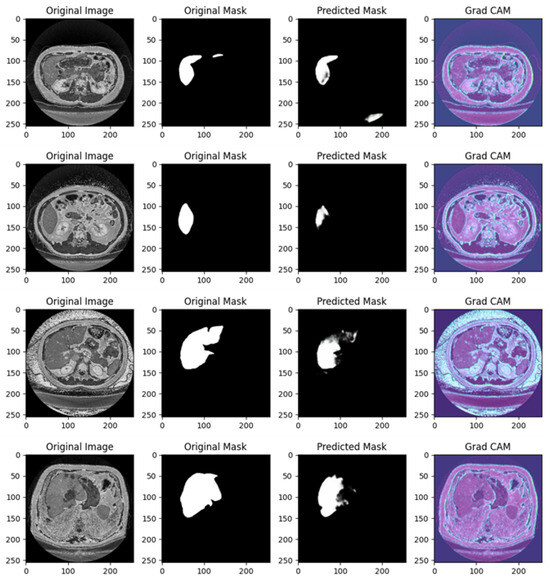

Figure 4 shows the segmentation capabilities every 25 epochs (for the first 100 epochs) of the U-Net model trained with the DI dataset.

Figure 4 shows, for different epochs, a set of images with the related segmentation mask predicted at a certain epoch. In particular, it shows the original images, original masks (i.e., the ground truth) and the predicted masks generated by a U-Net network trained for different numbers of epochs (1, 25, 50, 75, and 100 from top to bottom). The aim of the U-Net network is likely to segment a specific region of interest in the abdominal CT scans, i.e., the liver, based on the shape of the masks.

In the following, we provide a detailed analysis of the several masks generated for each epoch considered in Figure 4.

At 1 epoch, the original abdominal CT scan clearly shows several internal structures. The original mask marks the liver region in white, indicating its precise location and shape. However, the predicted mask is empty, suggesting that the U-Net model has not yet learned to recognize and segment the liver region. This is expected, as early stages of training often result in poor or no predictions.

At 25 epochs, the model begins to show some improvement. The original image is another abdominal CT slice, displaying a similar view. The liver region is again marked in white in the original mask, now with a small additional structure. The predicted mask, although incomplete and somewhat noisy, shows a partial segmentation of the liver. The areas predicted by the model are highlighted in pink, indicating that while there is some correspondence with the original mask, the model is still in the process of learning to isolate the liver region correctly.

By 50 epochs, the model’s performance significantly improves. The original image is another abdominal slice, and the liver, along with a small adjacent structure, is clearly demarcated in the original mask. The predicted mask now captures a larger portion of the liver, though there is still some noise around the region, signaling that the model is not yet fully refined. However, it has made substantial progress in recognizing and outlining the liver.

At 75 epochs, the model’s segmentation is much more accurate. The original image remains consistent with the others in this set. The liver region is again highlighted with a small additional white structure in the original mask. The predicted mask now closely approximates the shape of the liver shown in the original mask, with minimal noise. The model has become much better at distinguishing the target region, though a small amount of excess segmentation remains, indicating that further refinement is possible.

At 100 epochs, a new abdominal slice is introduced. However, this slice does not have an original mask, possibly indicating a different region or a non-target slice. The predicted mask is empty, similar to the prediction after 1 epoch. Since the original mask is missing, this suggests that the model is either not designed to segment this specific structure or has successfully learned not to apply a mask where no liver structure is expected.

As shown from Figure 4, as the number of epochs increases, the U-Net network demonstrates clear improvement in segmenting the liver. At 1 epoch, the model has no predictive capability. By 25 epochs, it starts to recognize relevant areas but is still noisy. From 50 epochs onward, the predicted masks align more closely with the original masks, with improved segmentation accuracy and reduced noise. The model at 100 epochs demonstrates the ability to avoid unnecessary predictions in slices where no liver is present, indicating the model has generalized better.

Training the U-Net model over more epochs results in significant improvements in segmentation quality, with the model learning to more accurately capture the target region (liver) and minimize noise. By 75 epochs, the predictions are highly accurate, and by 100 epochs, the model shows the ability to generalize to slices where no segmentation is required, which is a sign of good model training.